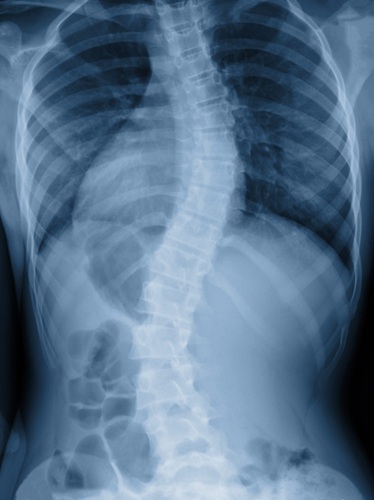

An image showing a spinal scoliosis

Scoliosis causes your spine to curve sideways instead of staying straight. Additionally, this condition creates an S-shape or C-shape in your back. Many people first notice uneven shoulders or hips. Furthermore, you might see that one shoulder blade sticks out more than the other. Some patients also experience their clothes fitting unevenly.

An X-ray image of a spinal scoliosis